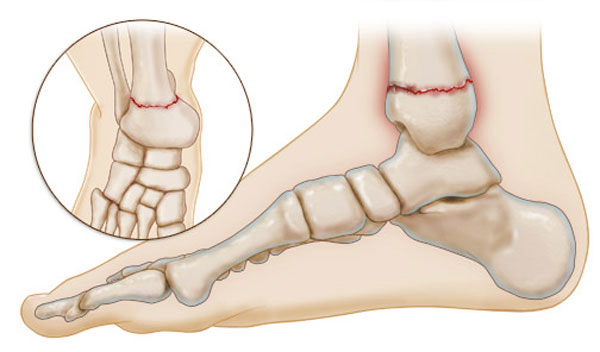

بهترین دکتر شکستگی مچ پا در مشهد + لیست 10 تایی